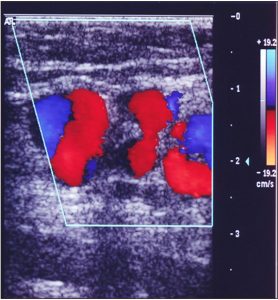

F — Вена подколенной ямки.

- Варикозные вены расположены в задне-медиальной или задне-латеральной части голени, проникают в фасцию в подколенной ямке.

- Может проявляться расширением притоков подколенной ямки или подкожной вены, если они связаны с сафенными венами.

- Может быть принята за МПВ.